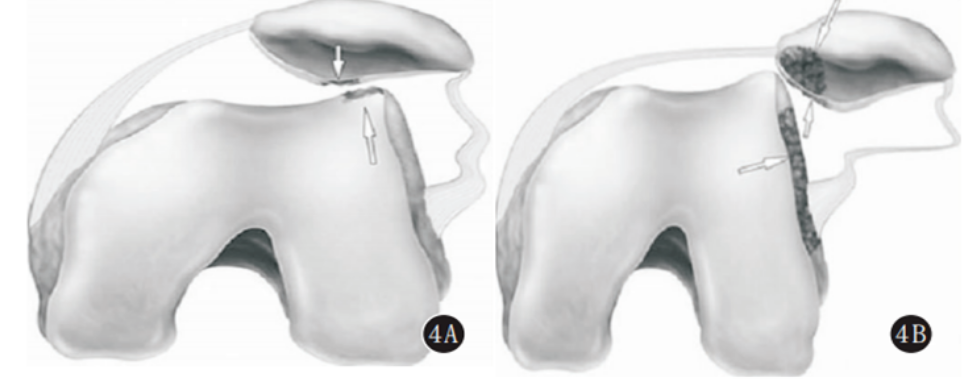

髌骨的稳定主要依靠 其周围结构的维持,而内侧支持带对髌骨的内侧稳定具有重要 的作用。髌内侧支持带为髌股关节主要稳定结构 , 可分为深浅两层 , 浅层较薄 , 深层包括内侧髌股韧带、内侧髌胫韧带及内侧髌半月板 韧带。当膝关节在站立伸直位 时,非直接创伤下,膝关节呈外翻或者内旋的屈曲状态,髌骨可向外侧移位,此时其外侧面会越过股骨的外侧髁部,因髌骨及其周围组织结构的特点,可直接撞击股骨外侧髁的外侧缘,导致相关部 位软骨及骨挫伤,严重可出现髌骨脱位状态。在股骨外侧髁的阻挡作用下,髌骨嵴以及髌骨的内侧下方会再一次撞击股骨外侧髁的外侧缘,从而导致软骨、骨的二次挫伤。

髌骨外侧脱位及髌骨复位过程中 , 髌骨内下缘及股骨外侧髁前外侧面碰撞挤压 , 主要造成髌骨内下缘及股骨外侧髁 前外侧面骨损伤及内侧支持带损伤。骨损伤包括骨挫伤及软骨及软骨下骨损伤 , 骨挫伤为骨髓水肿、出血及骨小梁微骨 折 , MRI 可见皮质下骨质内斑片状及线样稍长 T1 长 T2压脂高信号影。髌骨外侧脱位时 , 内侧支持带紧张 , 导致其损伤甚至撕裂 , 常发生于髌骨附着点及股骨附着点处 , 内侧支持带损伤时 , 表现为支持带增粗、扭曲、变形 , 边缘模糊或连续性中断。